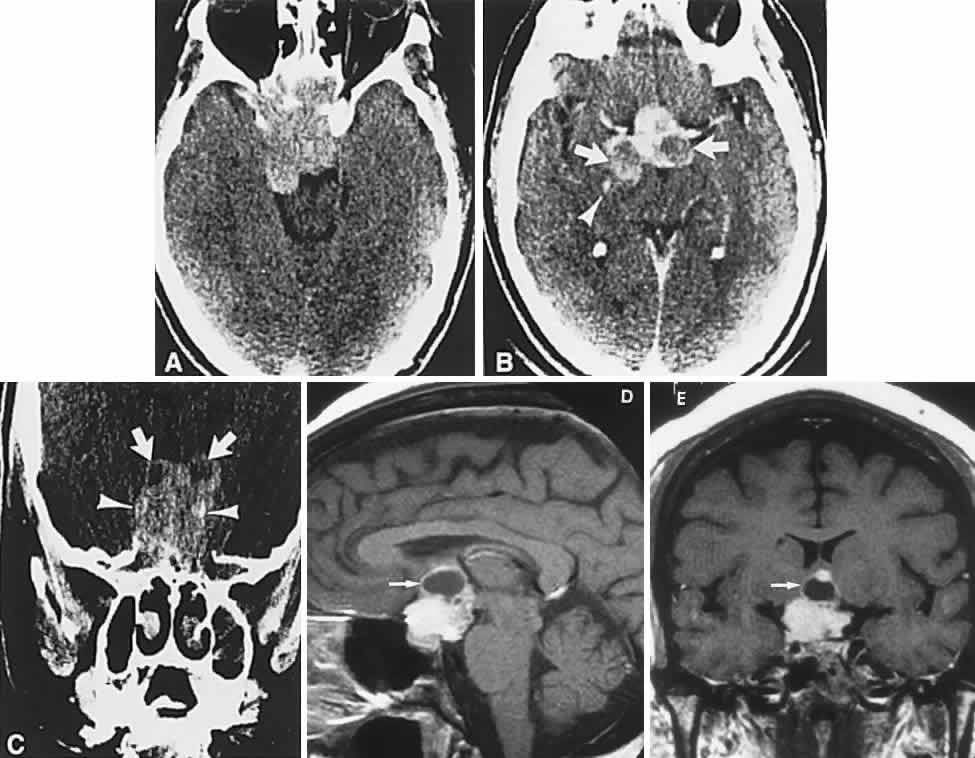

Clinical signs and symptoms include the following: acute onset of severe headache, often sickening frontal or retro-bulbar cephalgia, or other less disabling change in headache pattern; acute or rapidly progressing unilateral or bilateral (usually asymmetric) ophthalmoplegia due to rapid expansion into cavernous sinuses (see also Volume 2, Chapter 12); epistaxis or CSF rhinorrhea when the mass ruptures or erodes into the sphenoid sinus; complications of blood or necrosis debris in the CSF, with “pseudomeningitis”; rapid neurologic deterioration and obtundation, although patients need not be stuporous; and, greater or lesser degrees of hypopituitarism.62,63 Selective expansion laterally into the cavernous sinus may produce ophthalmoplegia without visual loss; selective expansion superiorly may produce visual loss without ophthalmoplegia. Almost without exception, enlargement of the sella is found even on plain skull film views; both CT and MRI detect fresh hemorrhage (Fig. 3), but MRI may fail to demonstrate acute hemorrhage unless specific sequences are employed (hemorrhage may be isointense on T1-weighted images and hypointense on T2-weighted images; in the subacute phase, extracellular methemoglobin should appear bright on both T1 and T2 sequences). Corticosteroid replacement and other supportive measures may be critical, and, in most instances, decompression through the sphenoid sinus is advisable, sooner rather than later. Bromocriptine has been suggested as a temporizing measure when signs and symptoms are modest and not progressing,64 and there are advocates65 for conservative management consisting of intravenous dexamethasone, so long as visual deficits are minimal or rapidly improve; otherwise decompressive surgery is required. Given the regularity with which pituitary apoplexy is often a delayed diagnosis, being confused with ruptured aneurysm or meningitis, for example, and that transsphenoidal surgery is a relatively simple undertaking, further procrastination in decompression of the compromised visual pathways is to be avoided.

Fig. 3. Neuroimaging of pituitary adenomas. A. Axial computed tomography (CT) section shows a round tumor mass filling the suprasellar cistern; ring enhancement (arrows) indicates subcapsular hemorrhage. B. Contrast-enhanced coronal CT section through a large invasive adenoma. Note encasement of the carotid artery (arrows) and the position of the middle cerebral artery above (arrowheads). C. Axial CT section shows lateral expansion into the cavernous sinuses (white arrows) and a necrotic cyst (black arrow). D. Subfrontal superior extent of the mass. Note the middle cerebral arteries. E. Magnetic resonance imaging of a large lobulated prolactinoma, with suprasellar extension. Note the distortion of the third ventricle (open arrows) and extension toward the temporal lobe (long arrow); the tumor has not involved the sphenoidal sinus (s). F. Chiasm (arrowheads) is draped on the superior surface of the tumor (TR, 550 milliseconds; TE, 26 milliseconds). G. Sagittal section shows suprasellar growth with the chiasm above (arrowheads); the sella (arrows) and sphenoidal sinus (s) are normal (TR, 850 milliseconds; TE, 26 milliseconds). H. Hyperintense signal (TR, 2000 milliseconds; TE, 60 milliseconds) indicates the partial cystic character. Sagittal (I) and axial (J) sections with head tilt to the right, in case of a large cystic adenoma with an interface level between newer blood (white arrow) and older blood (black arrow) (TR, 800 milliseconds; TE, 30 milliseconds). K. Signal difference is intensified (TR, 2100 milliseconds; TE, 80 milliseconds). L. Hemorrhage (bright signal, arrow) in a pituitary adenoma with headache and bitemporal field depressions. M. Without interventions, 2-month follow-up showed spontaneous involution, with normal pituitary gland (arrow), stalk, and chiasm.